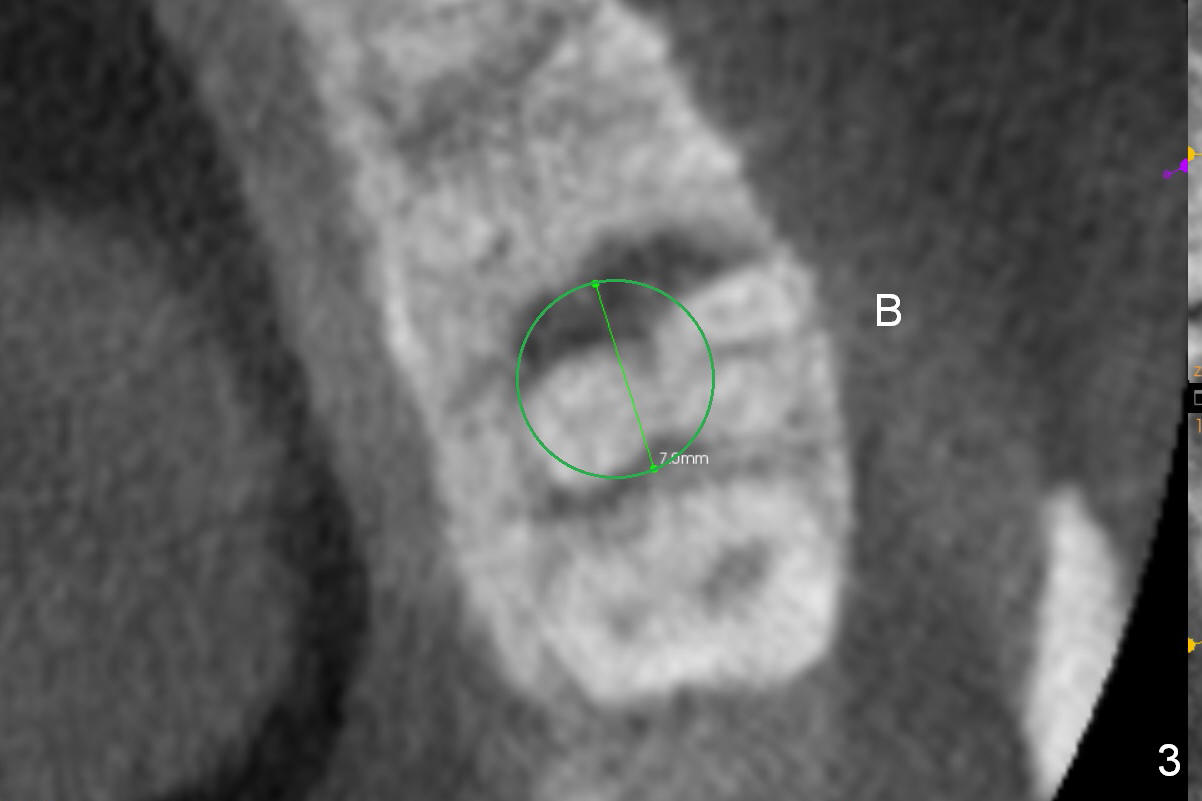

A 42-year-old lady (HJ) has advanced periodontitis at #15 (Fig.1 (CBCT sagittal section)). The buccal (B) plate is thin (Fig. 2 (coronal section), 3 (axial section)). The apical bone is also thin (Fig.1,2). A 7x10 mm implant is placed in a position so that the implant contacts the mesial, palatal and distal walls of the socket (treated with 2% Xylocaine with 1:50,000 Epinephrine) for primary stability (Fig.3). The buccal gap will be filled with Osteogen Plug apically (Fig.4 purple rectangles) and bone graft coronally (red circles). SM implant (Fig.4) is more tapered than UF one (Fig.2), easier to insert.